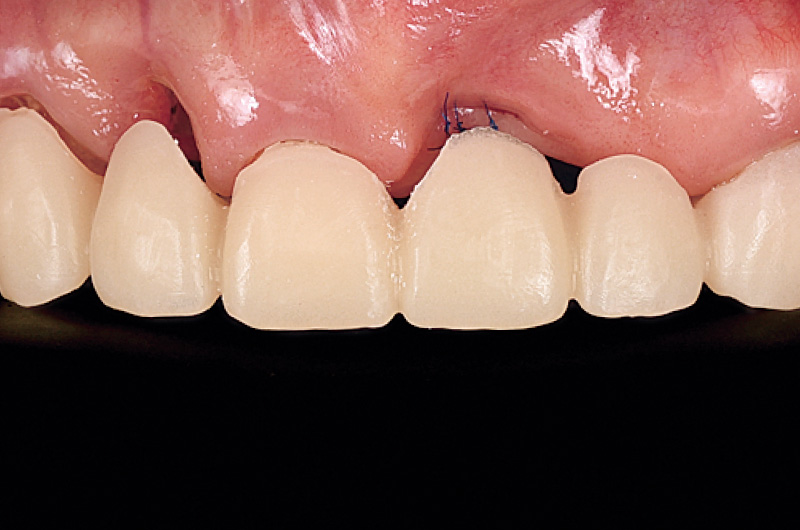

前歯は、②① ①2のロングスパンブリッジが装着されている。デンタルにて₁が歯根を取り囲むような透過像が確認された(図1)。

図1 21には、歯根を取り囲むような感染像を認める。22の根尖相当部にはGP様異物が確認できる。 -